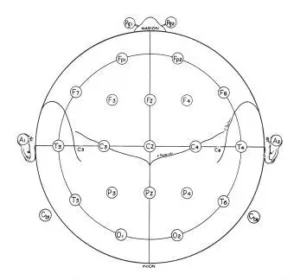

Anatomical studies were performed on the heads of cadavers to determine the cortical areas covered by each electrode position. Measurements were taken and the 10-20 system marked on the skulls, and electrodes were applied. Drill holes were placed through the skull and the underlying cortex was marked with India ink before removing the brain for examination. It was concluded that while there was some variability, the two principle fissures, central and sylvian, were within ±1cm of the marks shown on Fig.6.

Fig.4 the lateral view of left and right hemipshere showing all standard electrode psositions, omitting intermediate positions (such as C5 and C6) which are used only for special studies with more closely spaced electrodes. These drawings were made from a series of X-Ray projections with true lateral views. The location of principal fissurees was determined by silver clips placed at operation and bu other anatomical studies described in the text. The location pf pharyngeal electrodes (pg and Pg2) wal also obtained from X-Ray studies with these electrodes in place.

Fig. 6 A single plane projection of the head, showing all standard positions and the location of the rolandic and sylvian fissures. The outer circle was drawn at the level of the nasion and inion. The inner circle represents the temporal line of electrodes. This diagram provides a useful stamp for the indication of electrode placements in routine recording.